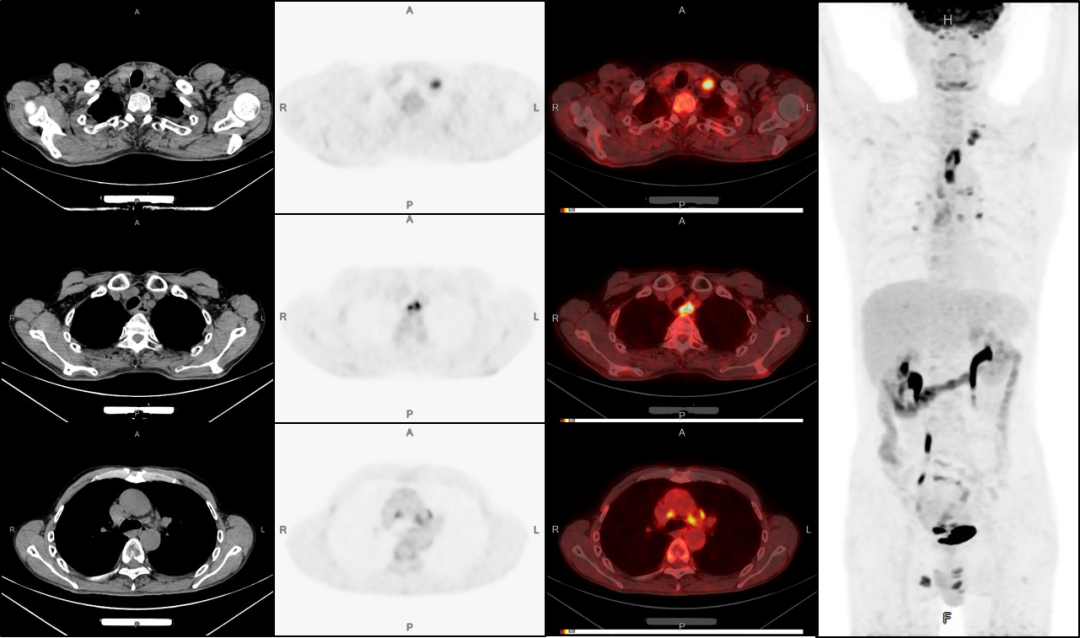

以上案例來均來自明峰醫(yī)療PET/CT。

明峰醫(yī)療作為全國首臺全數(shù)字化PET/CT的創(chuàng)造者,擁有自主研發(fā)全數(shù)字化探測器,承擔了國家科技部PET/CT核心技術專項課題,并獲得國家科技部專項科研基金和新型PET探測器架構(gòu)核心專利等,擁有領先高效的四大智能處理平臺。